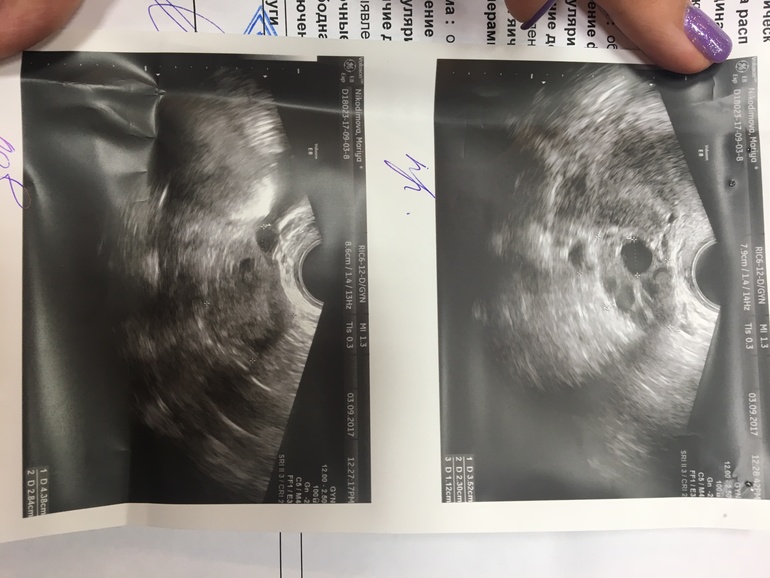

Привет, девочки, дождалась я 8 дц и пошла на фолликулометрию. Доктор сказала что никакого мультифолликулоза (который поставил предыдущий доктор) у меня нет. Сказала что в принципе все нормально и следующий мой визит на 11 дц. На всякий выкладываю результаты сюда, гляньте знающие, все нормально?) Может у нас все получится в этот раз?)

Предыдущий раз мне делали УЗИ малого таза и сказали что фолликул слишком много, а в этот раз я Ее спросила и она сказала количество фолликул в норме)

просто обычно пишут "до...шт.в срезе". если до 10, значит норма. если больше, но капсула яичника не утолщена и фолликулы также расположены, а не по контуру яичника, то МФЯ. если капсула утолщена, много мелких фолликулов по контуру яичника + задержки М и проблемы с гормонами, то спкя.